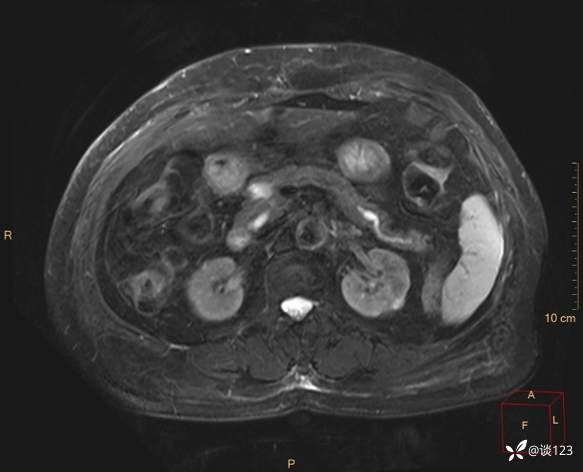

再做MRI

fsT2WI

cor T2WI

DWI

多期增强